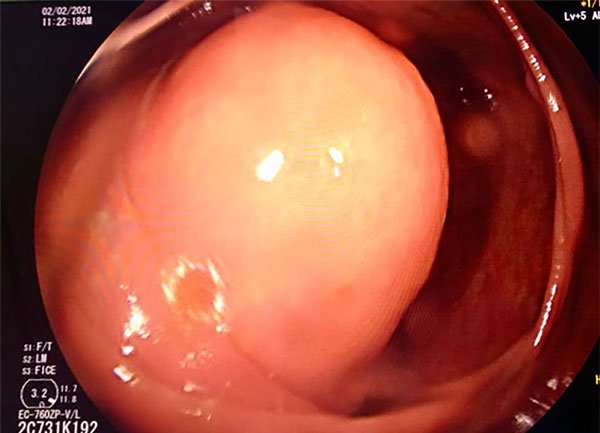

La videocolonoscopía muestra un abombamiento recubierto de mucosa de aspecto normal en topografía de válvula ileocecal, con “signo del cojín”. Se interpreta como lesión submucosa de la válvula ileocecal (Fig. 1).

Figura 1: Imagen endoscópica donde se evidencia un abombamiento recubierto de mucosa normal (signo del “cojín”), que se interpreta como lesión submucosa de la válvula ileocecal.